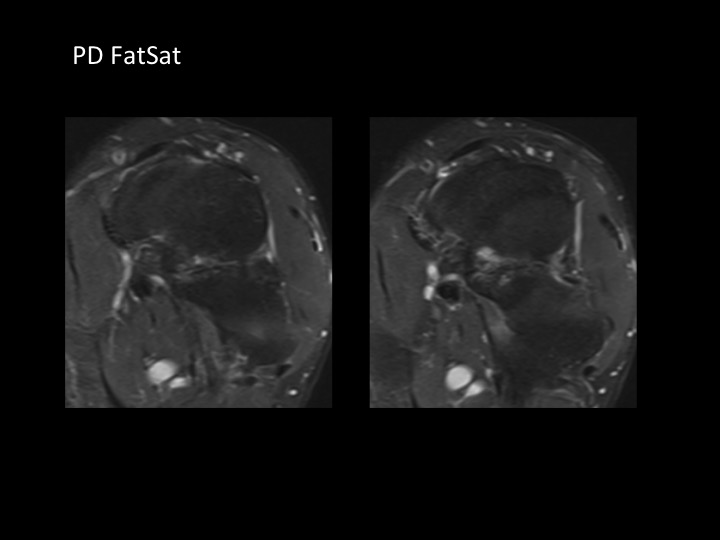

Although there have only been 9 cases of navicular-cuboid coalition reported up to 2012 (up to and including the reference for case #1390), here is another case in a 30M with bilateral non-osseous navicular-cuboid coalition (white arrows; changes more pronounced on the left). He has left-sided Haglunds deformity, which relates to his symptoms. Although the 4 cases reported in the reference from #1390 had midfoot pain, I am struck that this patient, and the 10 yr old from #1390 both present with hindfoot pain. I imagine the midfoot tarsal coalition might have a global impact on foot biomechanics.

navicular-cuboid coalition